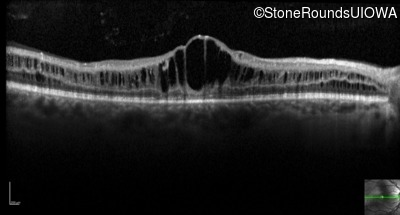

Optical Coherence Tomography - Left - 20/40

Exemplar / OCT Stack

OCT Stack